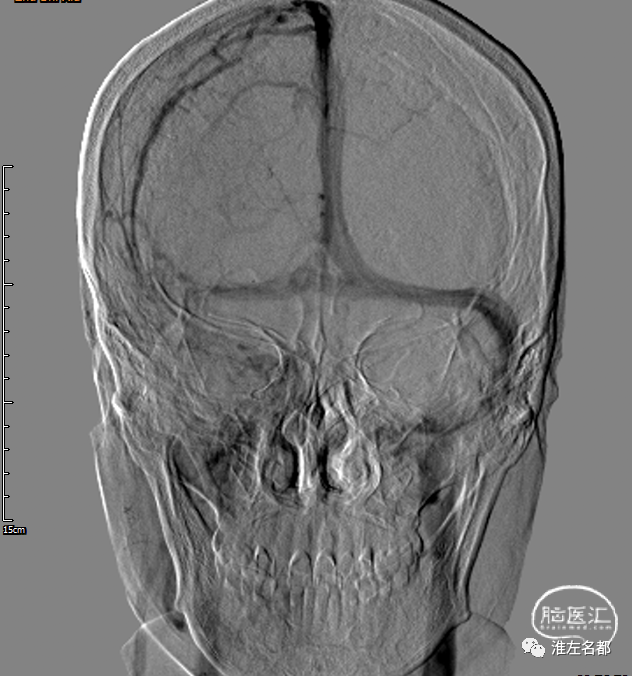

主动脉弓造影静脉晚期图像,

双侧颈内静脉、颈外静脉和上腔静脉显影通畅。

此为主动脉弓造影静脉晚期图像,

右侧左侧颈内静脉未见显影。